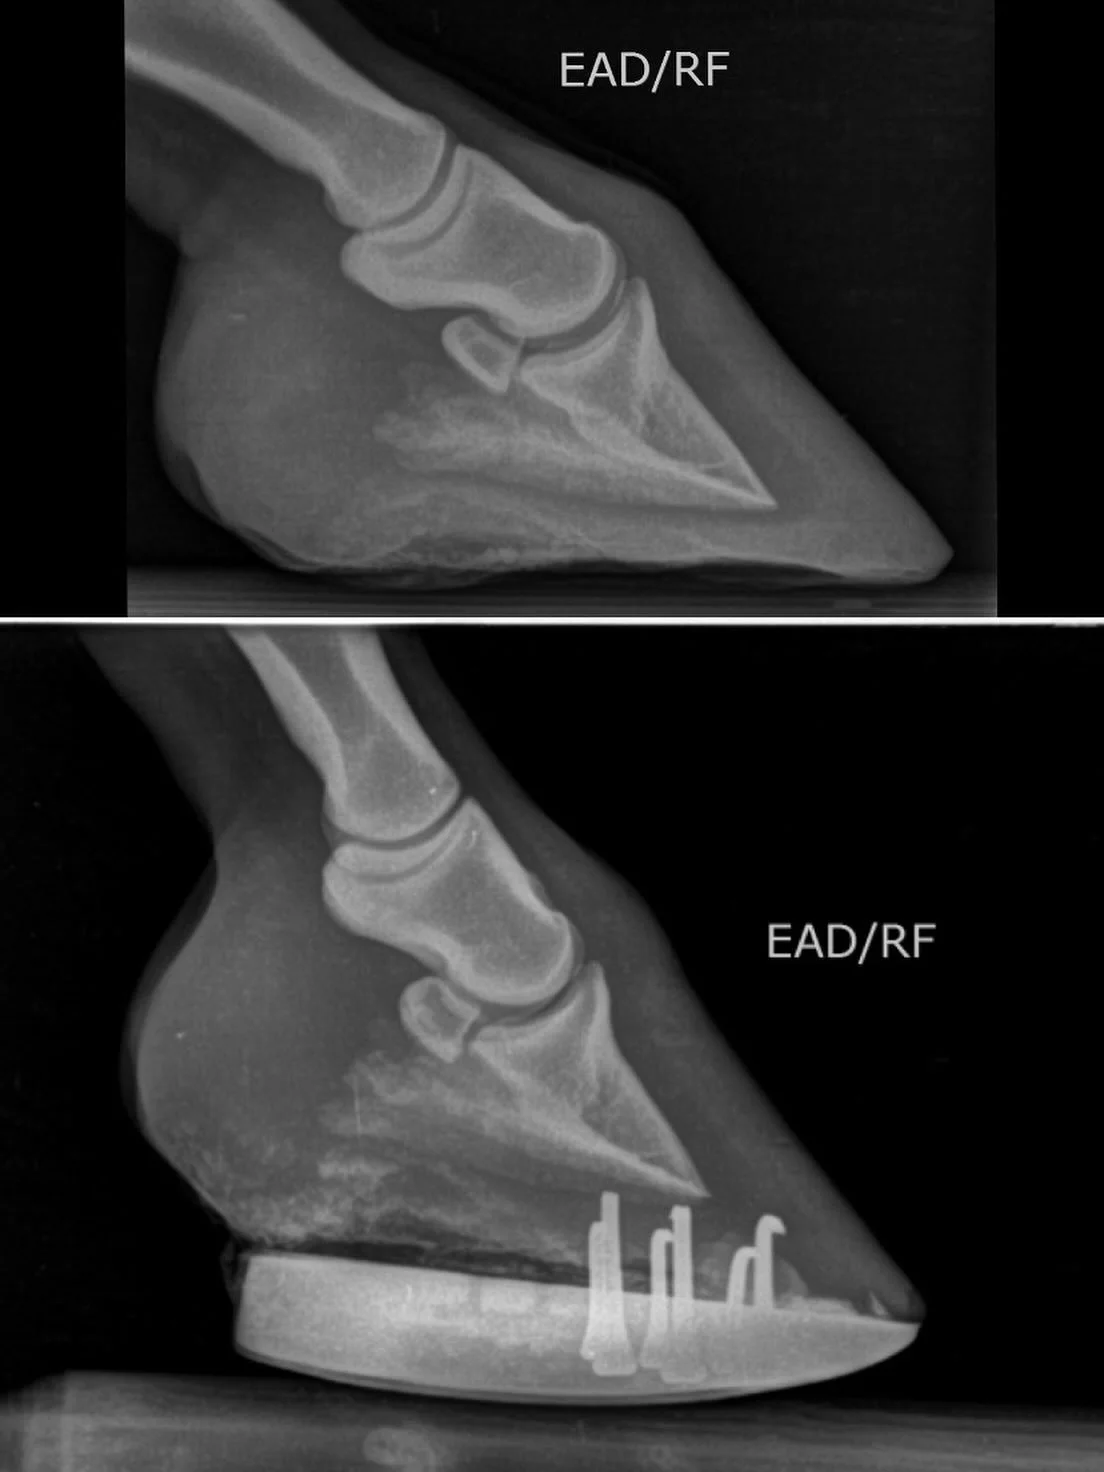

Síndrome navicular

Reconstrucción y estabilización del casco con materiales avanzados

Utilizamos fibras de vidrio y materiales técnicos de última generación para la reconstrucción de cascos, permitiendo estabilizar estructuras dañadas y proteger zonas comprometidas.

Fabricación de herraduras 3D personalizadas

En determinados casos, vamos un paso más allá gracias a la fabricación de herraduras 3D totalmente personalizadas. Esta tecnología nos permite:

Diseñar herraduras específicas para cada casco

Ajustarnos con precisión milimétrica a la morfología del animal

Corregir problemas biomecánicos complejos

Mejorar el confort del équido, especialmente en patologías crónicas, reduciendo tensiones, aportando estabilidad y facilitando una pisada más cómoda y segura.